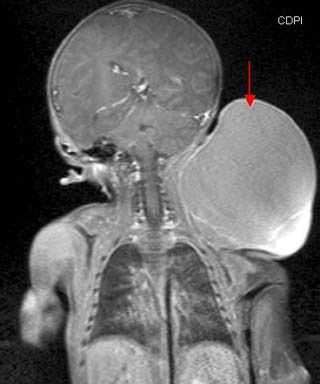

В процессе обследования особое значение имеет ультразвуковое исследование, назначаемое всем пациентам с имеющимися сосудистыми заболеваниями. Фиброларингоскопия назначается для исследования патологий сосудистых образований в глотке и гортани. МРТ является важным методом исследования при обширных поражениях в области головы и шеи. В ряде случаев при проведении многих исследований детям назначается седация, позволяя выполнять многие исследовательские процедуры практически безболезненно.

Лимфангиома у детей грудного возраста, младших возрастов диагностируется при помощи МРТ и компьютерной томографии на условиях общей анестезии.

- Магнитно-резонансная томография. По результатам МРТ мягких тканей удается точно определить степень поражения и морфологические характеристики сосудистой мальформации. Результаты исследования помогают сформировать правильную лечебную тактику, избежав необоснованных хирургических вмешательств.